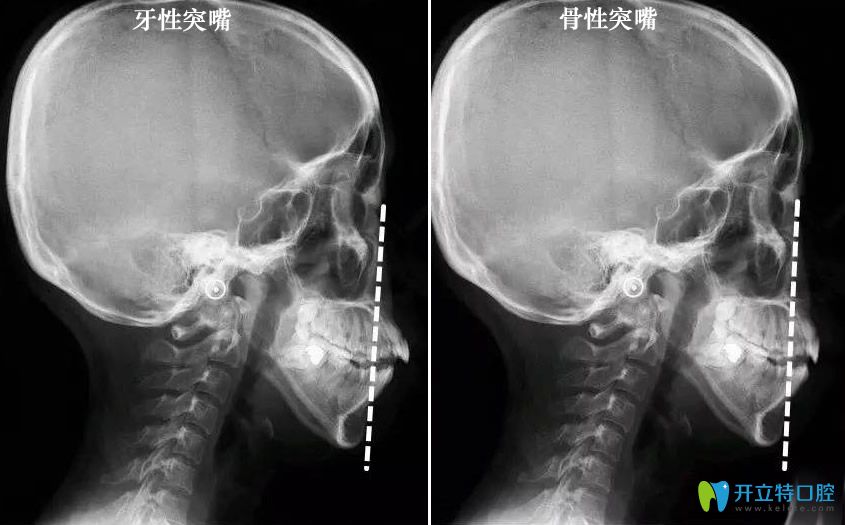

那么,怎么樣判斷嘴凸是骨性還是牙性?一眼讓你看明白!

【骨性突嘴和牙性凸嘴判斷對(duì)比圖】:↓↓

骨性突嘴和牙性凸嘴判斷對(duì)比圖

郭醫(yī)生表示,嘴凸牙性和骨性的區(qū)別在于,

單純的牙性突嘴,僅有牙齒向前突,?

牙齒長(zhǎng)軸角度傾斜過(guò)大,上唇和鼻子周?chē)遣还牡摹?/p>

而骨性突嘴,牙齒的上頜骨,還有鼻子周?chē)际窍蚯肮牡模?/p>

并且露出的牙齒比較多,從面相上來(lái)看,嘴唇是包不住牙齒,

骨性齙牙在笑的時(shí)候很明顯,有些整顆牙齒和牙齦會(huì)露出來(lái)。